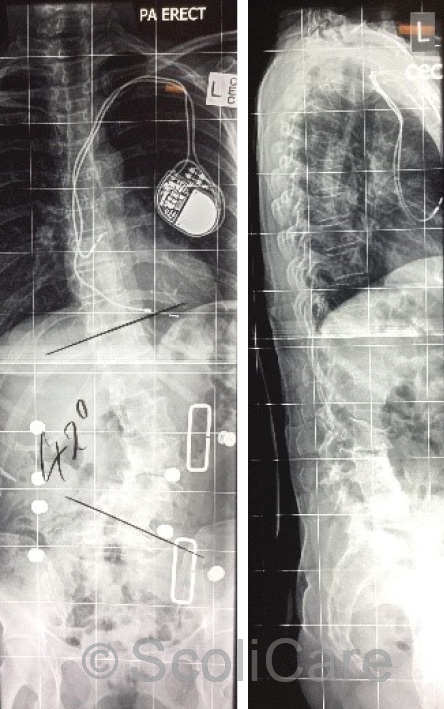

In-brace photos taken at the time of the brace fitting demonstrated a significant improvement in the patient’s sagittal and coronal postural balance. In-brace x-rays taken soon after the brace fitting appointment indicated a reduction in the patient’s scoliosis and an improvement in the sagittal balance (Figure 3). The patient was provided with instructions for donning and doffing and cleaning the orthosis. Brace wear was gradually increased by two hours each day up to the patient’s tolerance.

Figure 3: Posteroanterior in-brace x-ray with a 42° left lumbar scoliosis (Left),

Lateral in-brace x-ray highlighting an improvement sagittal balance (Right).